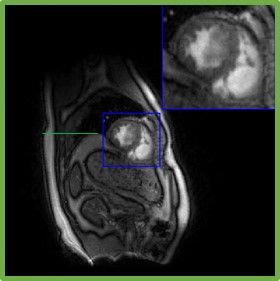

Figure 10: Illustration of the framework of the proposed scheme with d=40𝑑40d=40. We plot the latent variables of 150 frames in a time series. We showed four different phases in the time series: systole in End-Expiration (E-E), systole in End-Inspiration (E-I), diastole in End-Expiration (E-E), and diastole in End-Inspiration (E-I). The latent vectors corresponding to the four different phases are indicated in the plot of the latent vectors.

Finally, we illustrate the proposed approaches in Fig. 9 and Fig. 10, respectively. The proposed approach decoupled the latent vectors corresponding to the cardiac and respiratory phases well, as shown in the representative examples in Fig. 9 (a) and Fig. 10 (a).